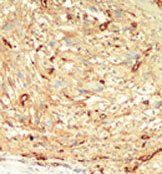

Supportive validation

- Submitted by

- Acris Antibodies GmbH (provider)

- Main image

- Experimental details

- Formalin-fixed and paraffin-embedded human cancer tissue reacted with the primary antibody, which was peroxidase-conjugated to the secondary antibody, followed by DAB staining.